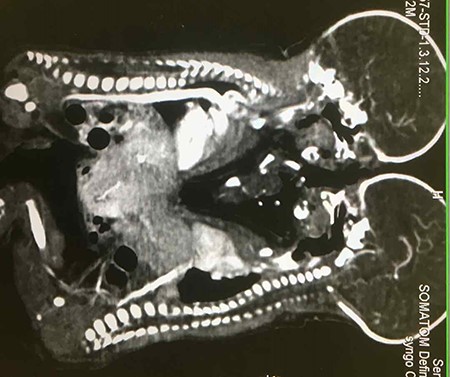

Ultrasonography of abdomen revealed fusion of liver but separate organ systems. A contrast computed tomography (CT) scan showed a large fusion in livers with secondary vascular connections, and twin L’s vena cava was pulled by the conjoined liver anteriorly (Fig. 2). Other organs were not shared. A 2D echo study of twin R revealed small Patent ductus arteriosus (PDA), while twin L had small atrial septal defect (ASD) with PDA. Blood investigations revealed haemoglobin (Hb) of 14.7 g/dl for Twin R and 13.5 g/dl for Twin L, with normal biochemistry values for both.

A contrast CT scan showing differential enhancement of livers of both twins and pulled vena cava for left twin.